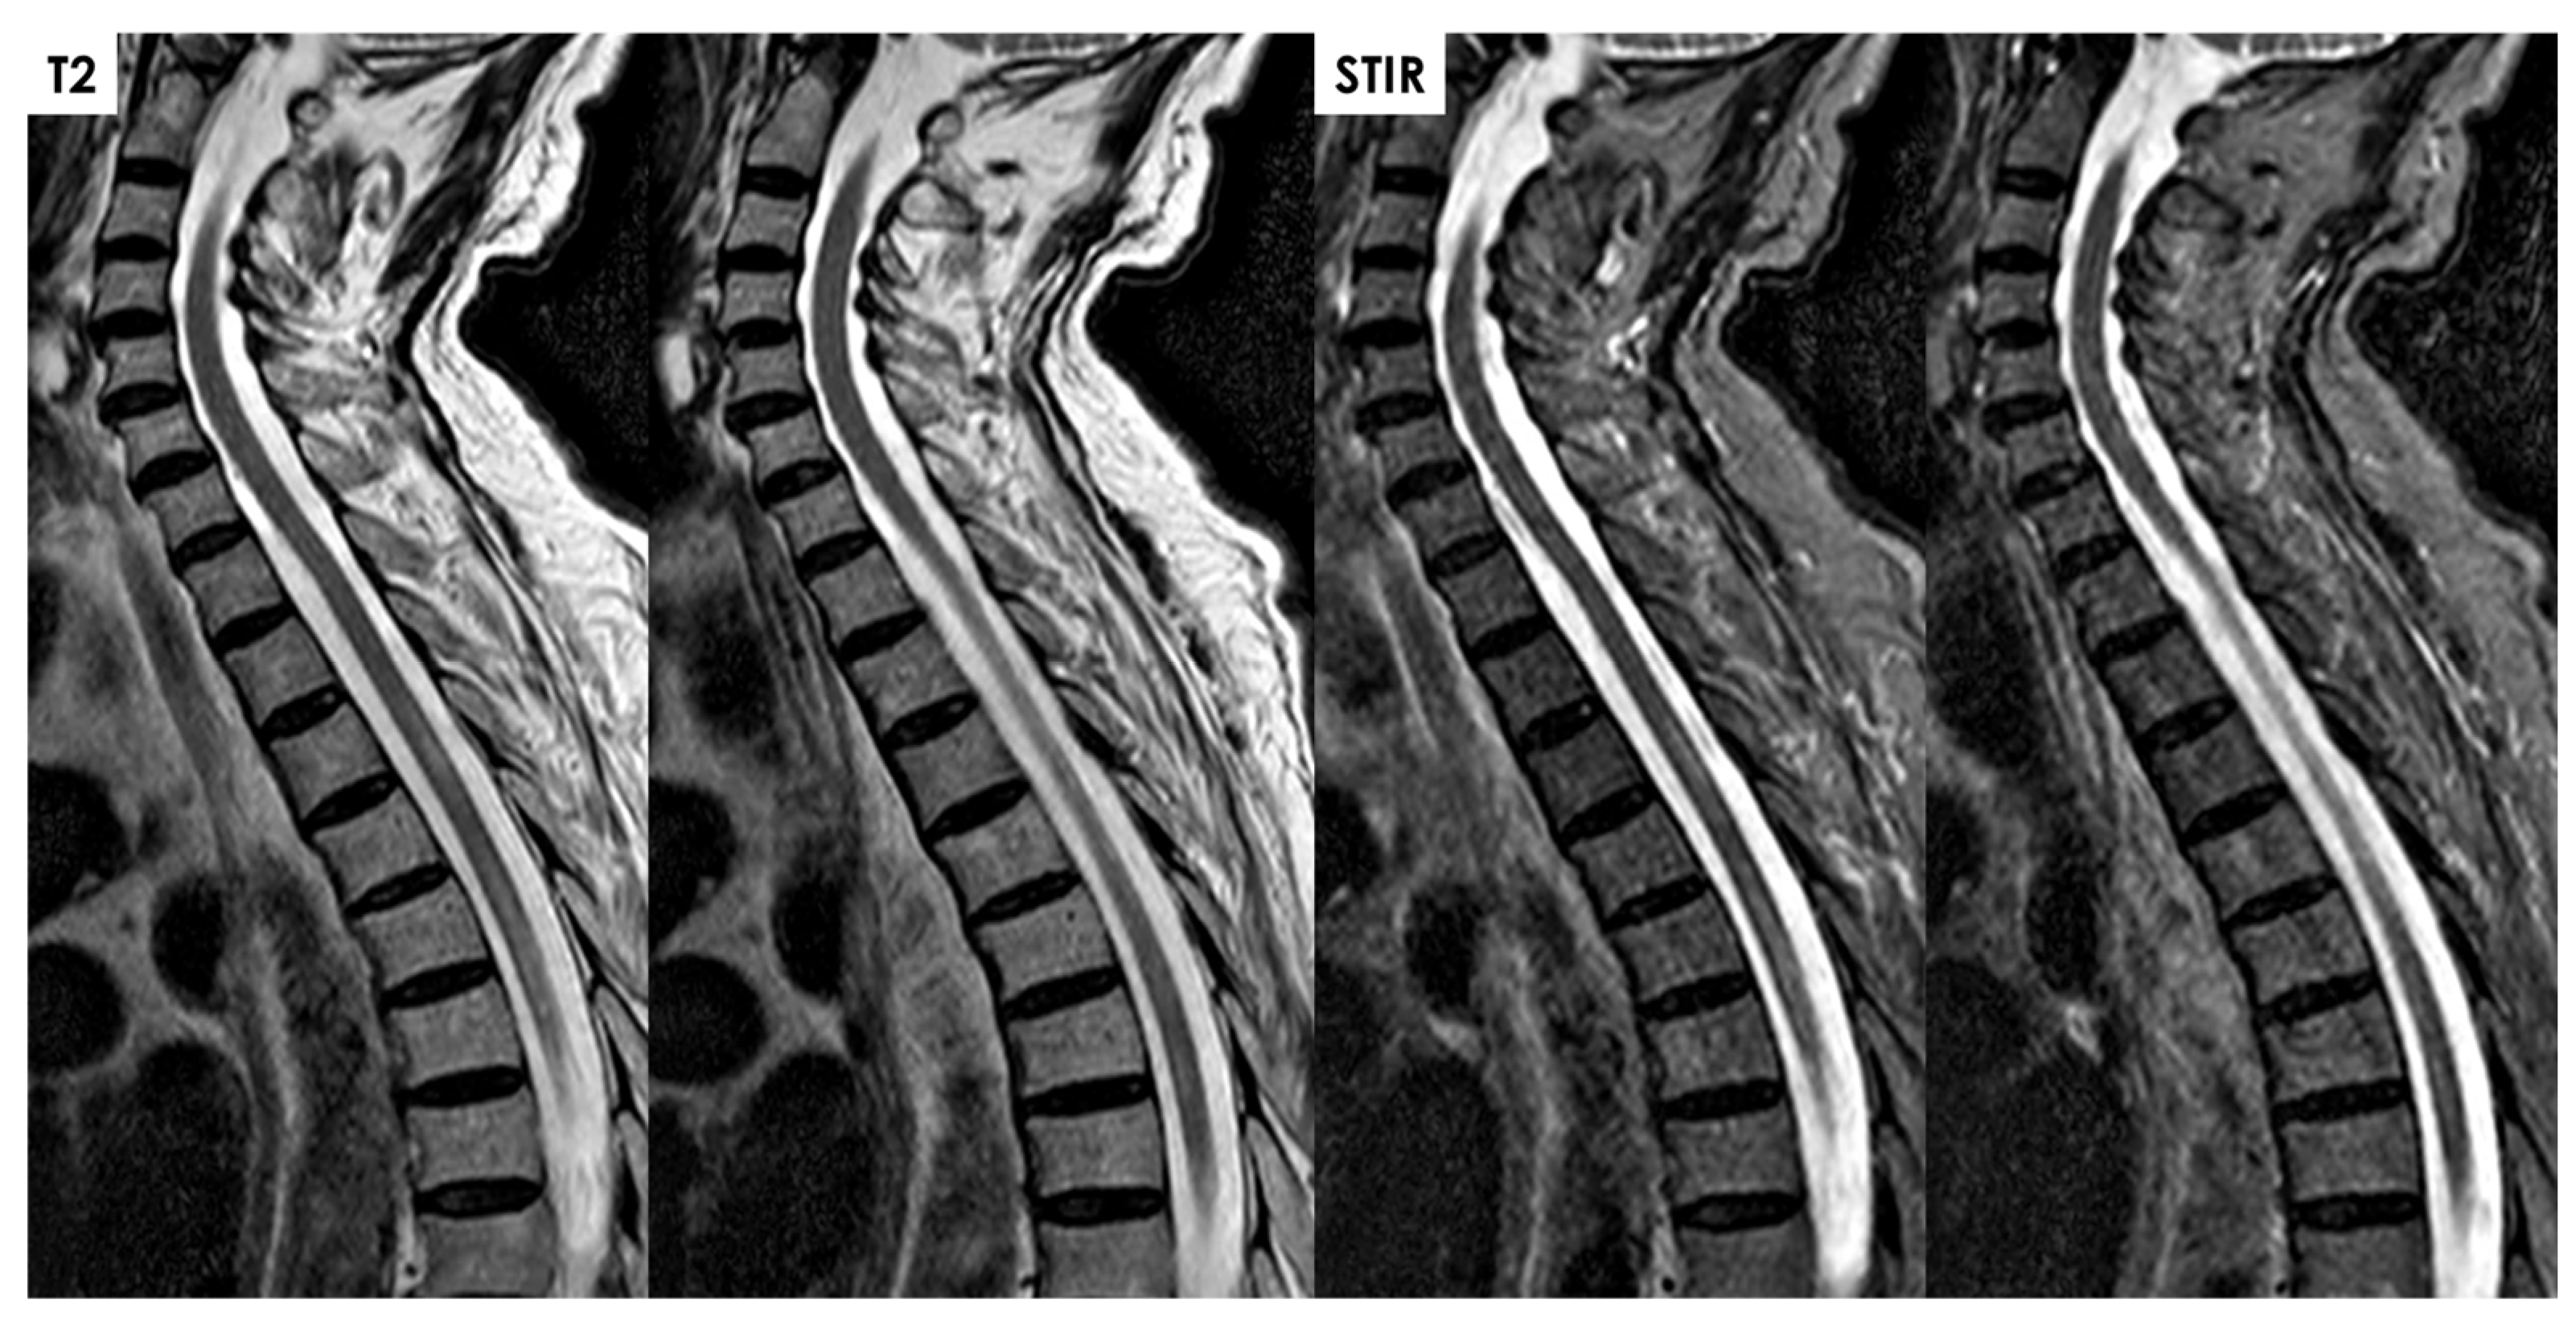

- In the hyperacute and acute phases, parenchymal T2-hyperintensity appears non-expansile, thin, and pencil-like on sagittal images;

- In the later acute and early subacute phases, spinal cord enlargement may occur;

- Parenchymal enhancement, often linear and involving the anterior gray matter, may appear in the acute–subacute phase;